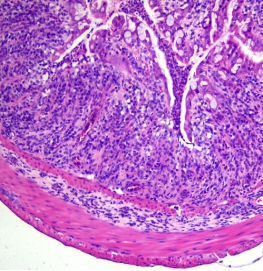

- Poor coat condition 2) Pathological Changes

- Significant shortening of the colon

- Mucosal thickening

- Lymph node enlargement

- Loss of goblet cells

- Loss of crypt structure

- Adenomatous polyps and tumor-like changes in some animals